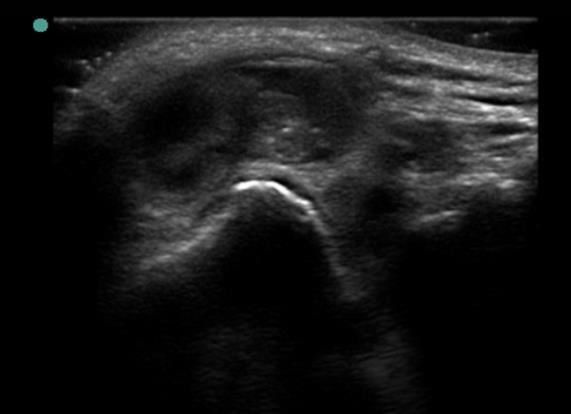

Shoulder Acromioclavicular (AC) Joint Ganglion Image